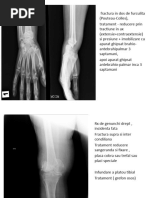

[Link] de epifiza distala de radius

normal, radiusul este mai lung decat cubitus; pe Rx in patologie sunt egale

mana apare in dos de furculita (vezi poza)

reducere: se trage de police + urmatoarele 2 degete

gips (imobilizare 4 sapt ptr fractura fara deplasare, respectiv 6 sapt ptr cea cu deplasare)